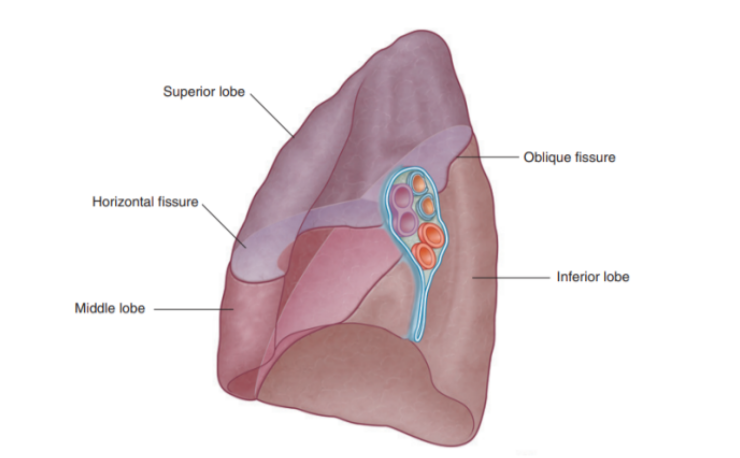

Fisssures of right lung

Has 2 fissures (formed by invaginations of the visceral pleura) —

Oblique fissure

Separates inferior lobe from superior & middle lobe

Horizontal fissure —

Separates superior lobe from middle lobe

Can be easily landmarked and correspond to specific ribs — important as they delimit zones of ascolatation

Lobes of right lung

Has 3 lobes — superior, middle, and inferior

Lobal attachment to surrounding mediastinal structures —

Superior lobe — in contact with the upper part of the anterolateral wall and the apex of this lobe projects into the root of the neck

Surface of the middle lobe — adjacent to lower anterior & lateral wall

Costal surface of inferior lobe — in contact with the posterior & inferior walls

Important structures in the mediastinum & root of neck that are adjacent to medial surface of right lung

Heart

Inferior & Superior vena cava

Azygos vein

Esophagus

Note about subclavian vessels & right lung

The right subclavian artery & vein arch over & are related to the superior lobe of the right lung as they pass. over the dome of the cervical pleura & into the axilla

Surface anatomy relating to the fissures and lobes

Palpable surface landmarks —

Can be used to visualize the normal outlines of the pleural cavities & lungs & to determine the positions of the pulmonary lobes & fissures —ex.

Margins of lungs related to ribs

Oblique fissure position —

Located in the midline, near the spine of vertebrae TIV, moves laterally downwards crossing fourth and fifth intercotal spaces and reaches VI laterally

Horizontal fissure(right side) —

Follows the contour of rib IV and its costal cartilage

Oblique fissures on both sides follow the contour of rib VI and its costal cartilage